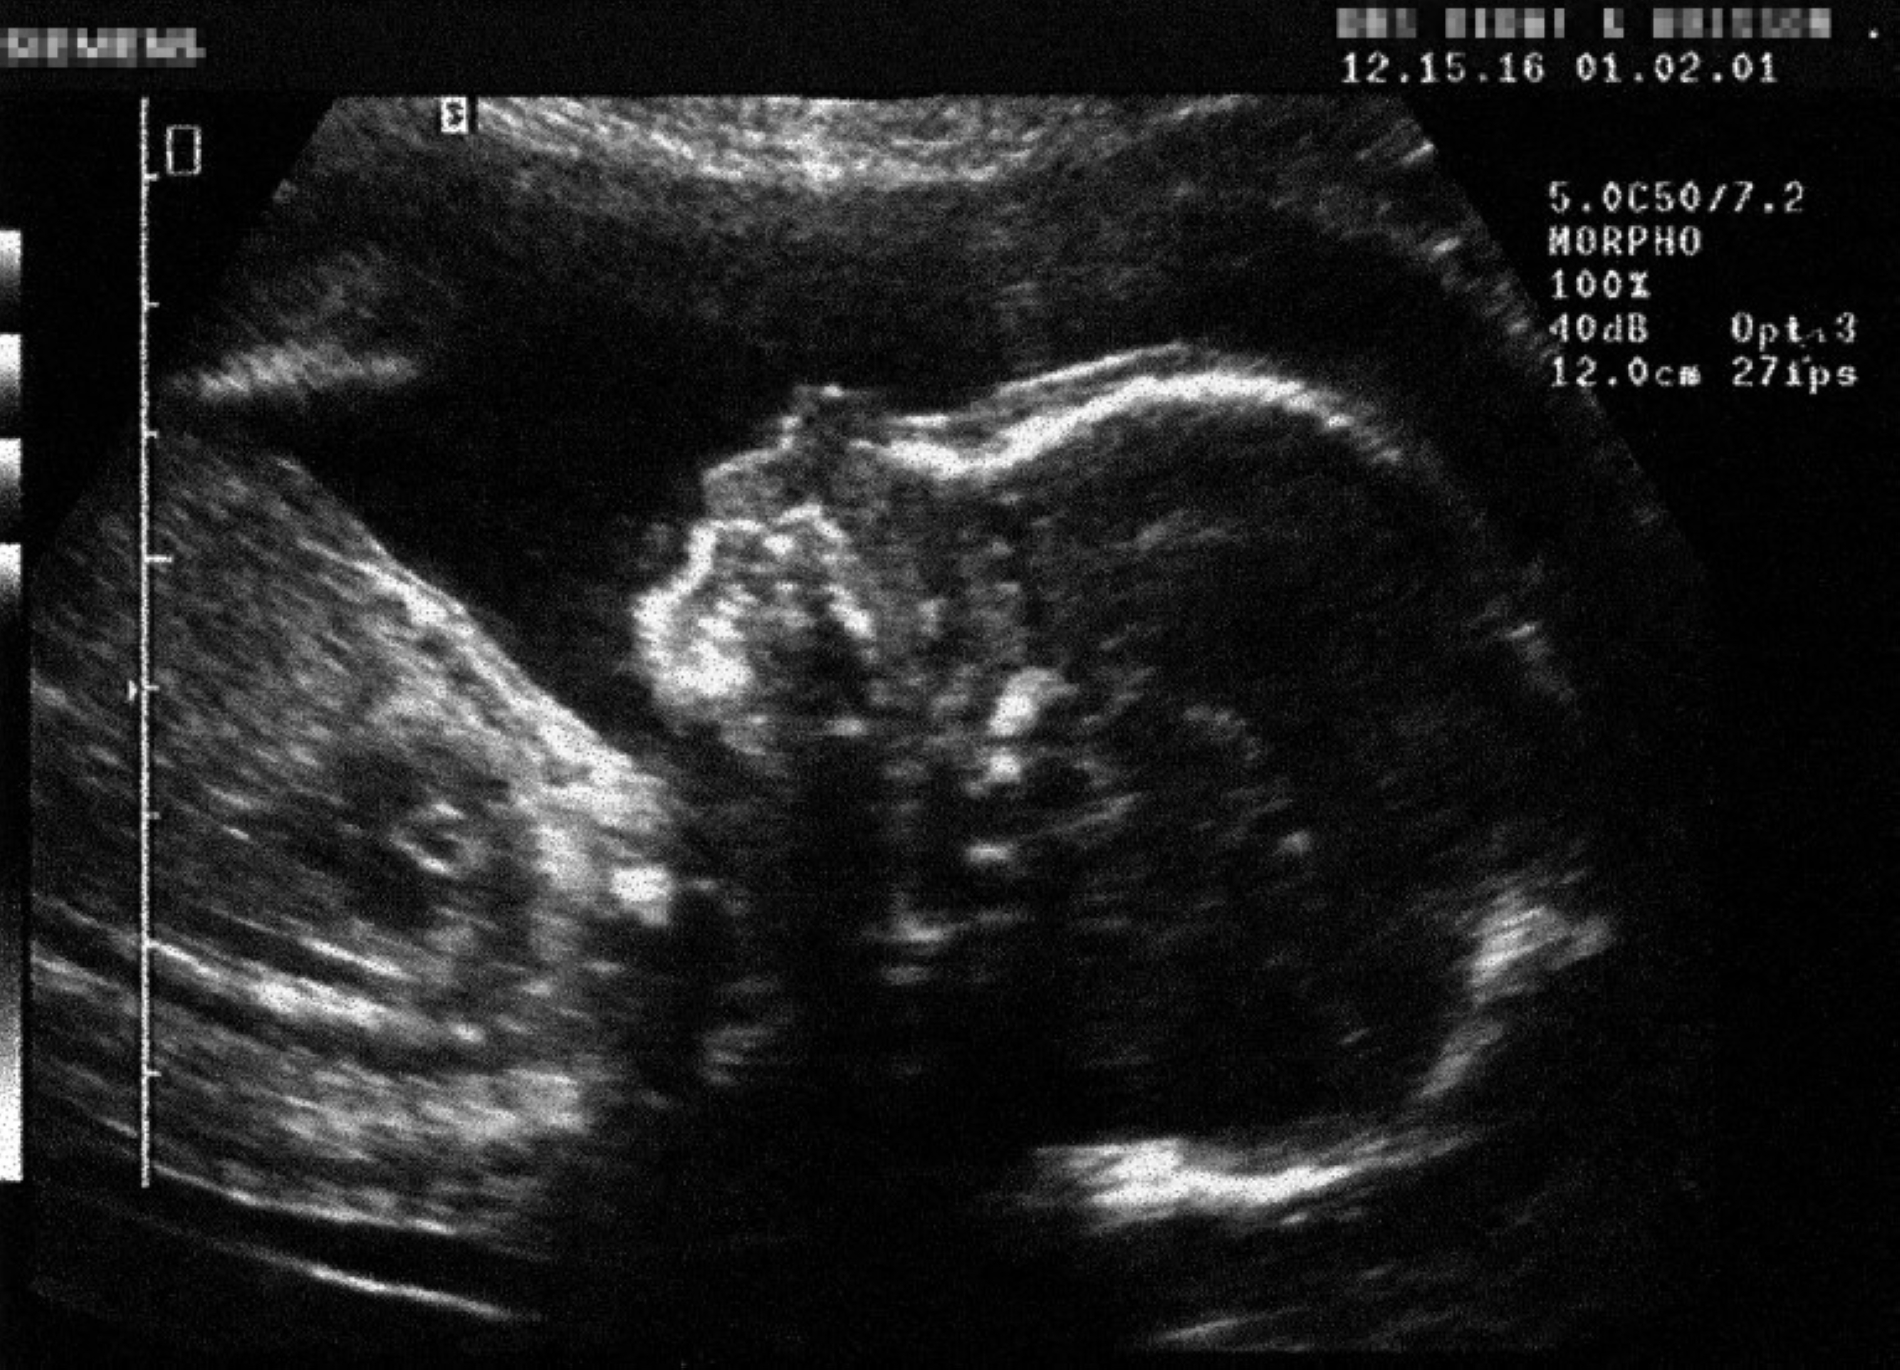

Researchers gathered data on dietary habits, tracked time to conception (as an indicator of fertility), and performed ultrasound scans to measure embryonic growth and yolk sac size in the seventh, ninth, and eleventh weeks. The findings suggest that UPFs may have a direct and noticeable effect on male fertility, with higher consumption associated with reduced fertility and a longer time to conception.

Among women, the study found no direct association between UPF consumption and reduced fertility or delayed conception, but it did reveal early effects on embryonic development. The embryos of women who consumed more UPFs were found to grow at a slightly slower rate, with a smaller yolk sac—the essential structure that nourishes the embryo during the first weeks of pregnancy.

The yolk sac plays a vital role in early pregnancy, as the first structure to nourish the embryo before the placenta is fully formed. It supplies essential nutrients and oxygen, supports the production of early blood cells, and contributes to the initial development of organs. Its size and shape are among the key indicators physicians rely on when assessing the health of a pregnancy in its earliest weeks. Any change in its size or function, however subtle, may have an early influence on embryonic development.